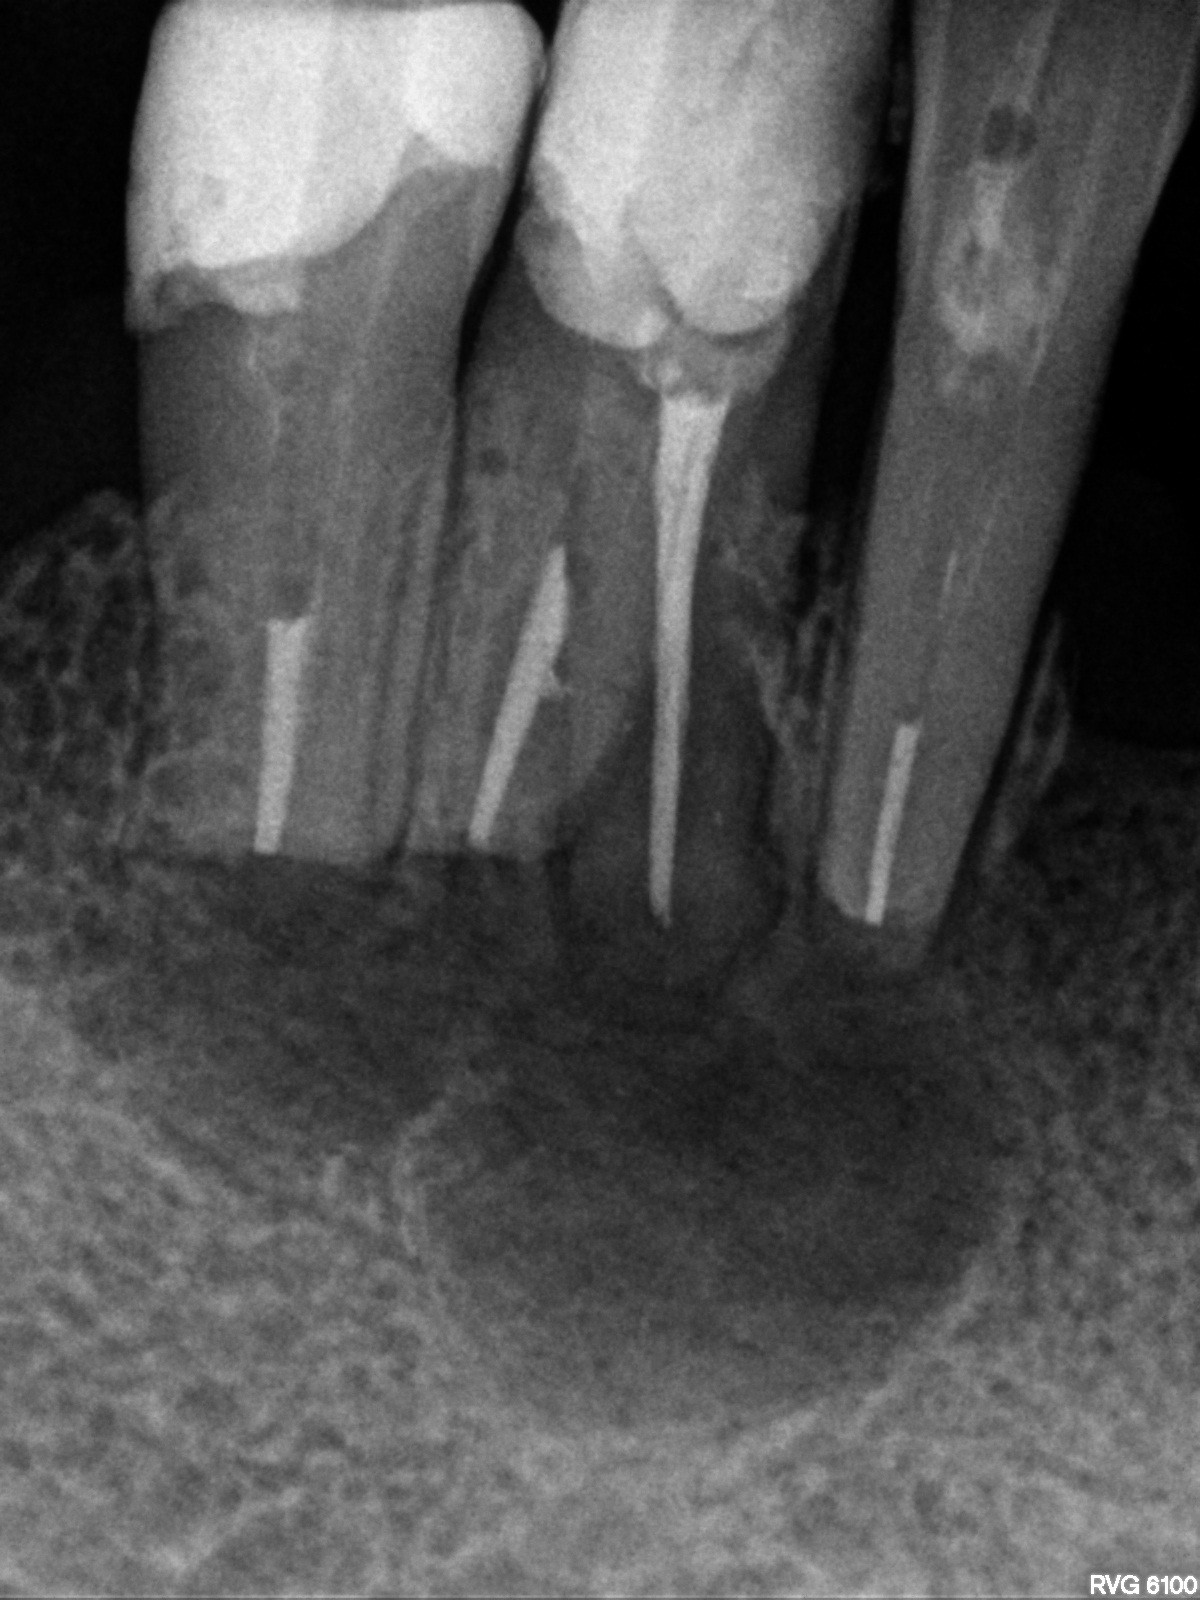

Bogata w płytki i leukocyty fibryna jest stosowana w regeneracji tkanek od ponad 15 lat. Pozytywny wpływ PRF (platelet-rich fibrin) na regenerację tkanek miękkich jest niewątpliwy, bezsporny i częściowo udowodniony w badaniach klinicznych i analizach biochemicznych. Wpływ PRF na regenerację tkanki kostnej jest obserwowany klinicznie, ale nadal niedostatecznie poznany jest mechanizm tego zjawiska.

Platelet- and leukocyte-rich-fibrin has been used in regeneration of tissue for more than 15 years. The positive influence of PRF on the regeneration of soft tissue is undoubtedly, without question and partially proven in clinical studies and biochemical analysis. Influence of PRF on regeneration of bone tissue is observed clinically but the mechanism of this phenomenon is still not sufficiently known.